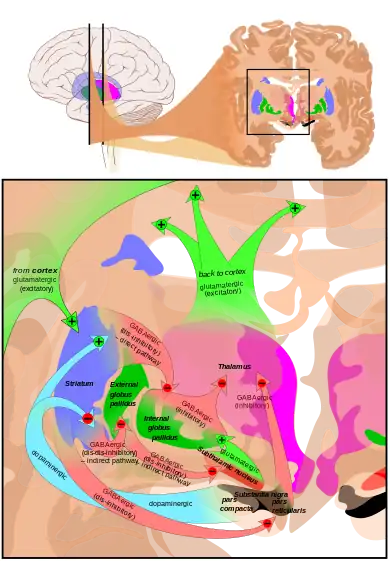

The subthalamic nucleus receives its main input from the external globus pallidus (GPe),[8] not so much through the ansa lenticularis as often said but by radiating fibers crossing the medial pallidum first and the internal capsule (see figure). These afferents are GABAergic, inhibiting neurons in the subthalamic nucleus. Excitatory, glutamatergic inputs come from the cerebral cortex (particularly the motor cortex), and from the pars parafascicularis of the central complex. The subthalamic nucleus also receives neuromodulatory inputs, notably dopaminergic axons from the substantia nigra pars compacta.[9] It also receives inputs from the pedunculopontine nucleus.

Efferent targets

The axons of subthalamic nucleus neurons leave the nucleus dorsally. The efferent axons are glutamatergic (excitatory). Except for the connection to the striatum (17.3% in macaques), most of the subthalamic principal neurons are multitargets and directed to the other elements of the core of the basal ganglia.[10] Some send axons to the substantia nigra medially and to the medial and lateral nuclei of the pallidum laterally (3-target, 21.3%). Some are 2-target with the lateral pallidum and the substantia nigra (2.7%) or the lateral pallidum and the medial (48%). Less are single target for the lateral pallidum. In the pallidum, subthalamic terminals end in bands parallel to the pallidal border.[10][11] When all axons reaching this target are added, the main efference of the subthalamic nucleus is, in 82.7% of the cases, clearly the internal globus pallidus (GPi).

Lateropallido-subthalamic system

Strong reciprocal connections link the subthalamic nucleus and the external segment of the globus pallidus. Both are fast-spiking pacemakers. Together, they are thought to constitute the "central pacemaker of the basal ganglia"[16] with synchronous bursts.

Some axons from the lateral pallidum go to the striatum.[18] The activity of the medial pallidum is influenced by afferences from the lateral pallidum and from the subthalamic nucleus.[19] The same for the substantia nigra pars reticulata.[11] The subthalamic nucleus sends axons to another regulator: the pedunculo-pontine complex (id).

Function

The function of the STN is unknown, but current theories place it as a component of the basal ganglia control system that may perform action selection. It is thought to implement the so-called "hyperdirect pathway" of motor control, contrasting with the direct and indirect pathways implemented elsewhere in the basal ganglia. STN dysfunction has also been shown to increase impulsivity in individuals presented with two equally rewarding stimuli.[24]